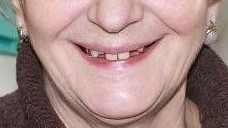

21 работа в портфолио